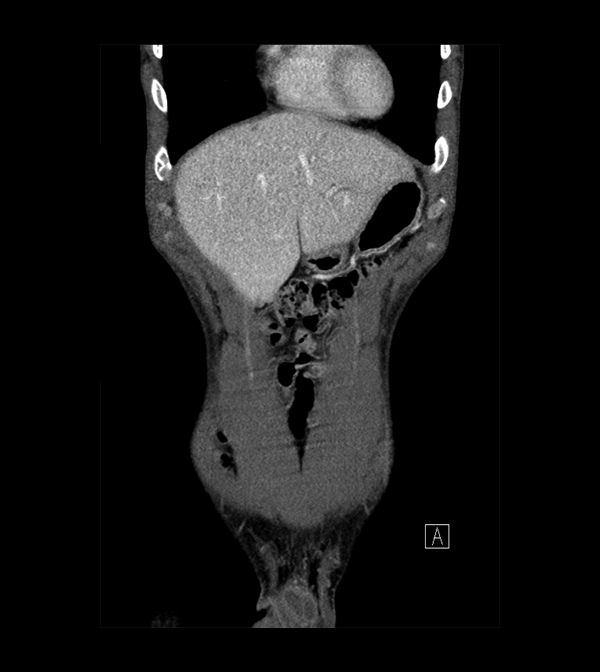

Body

Covers abdominal CT anatomy.